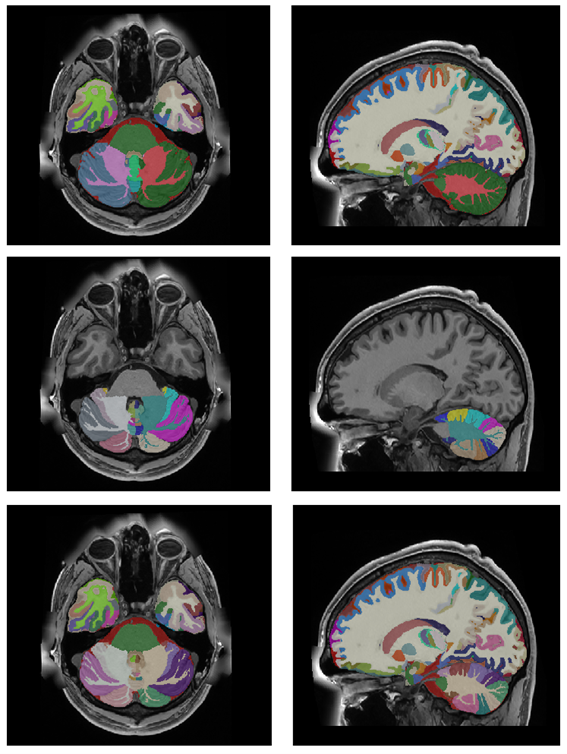

After the whole integration process, we generate the corresponding label maps at multiple scales combining the corresponding labels (from substructure to structure, then to tissue and finally to organ (ICV). Figure 11 shows an example of the new holiBrain protocol. The substructure scale has 350 labels, the structure scale has 54 labels, the tissue scale has 9 labels and finally ICV has 1 label.

Refer to caption

Figure 11: From Top to bottom: ICV (1 label), tissues (9 labels), structures (54 labels) and substructures (350 labels).